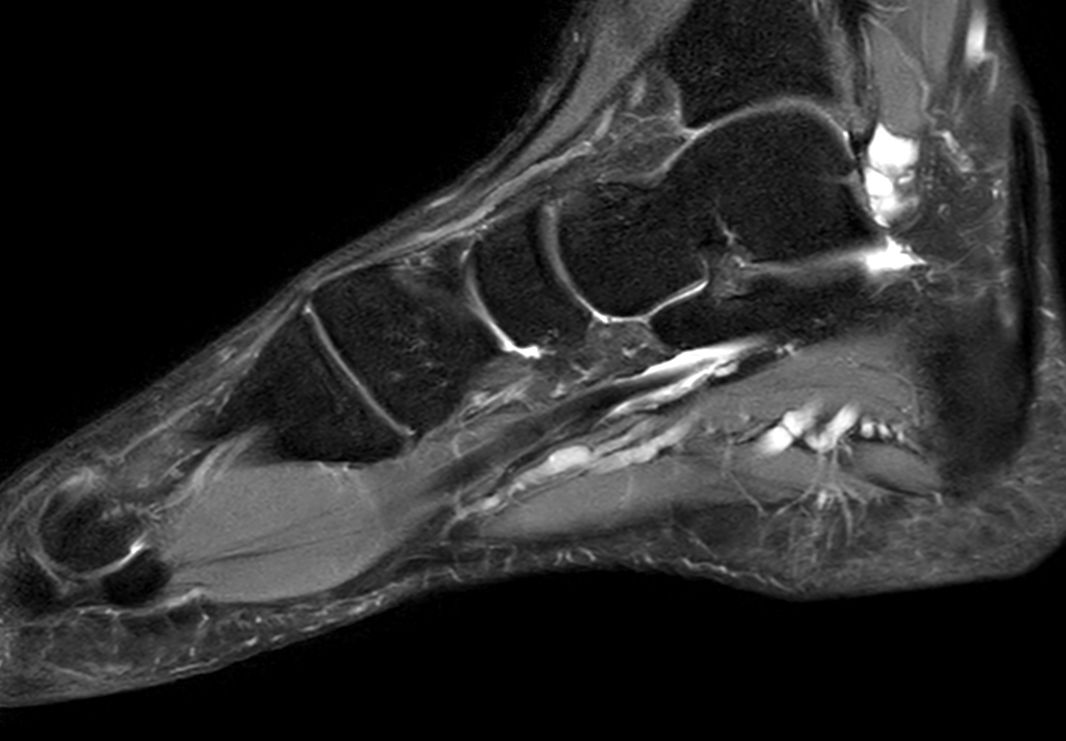

Foot with plantar fascitis

Sagittal PDw TSE mDIXON XDCompressed SENSE